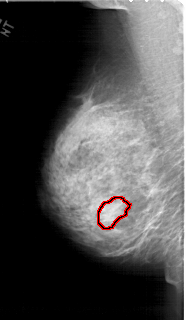

A_1453_1.RIGHT_CC

RIGHT_CC LINES 5986 PIXELS_PER_LINE 3241 BITS_PER_PIXEL 12 RESOLUTION 43.5 NON_OVERLAY

FILE: A_1453_1.LEFT_CC.OVERLAY

TOTAL_ABNORMALITIES 1

ABNORMALITY 1

LESION_TYPE MASS SHAPE LOBULATED MARGINS OBSCURED

ASSESSMENT 4

SUBTLETY 2

PATHOLOGY BENIGN

TOTAL_OUTLINES 1

BOUNDARY